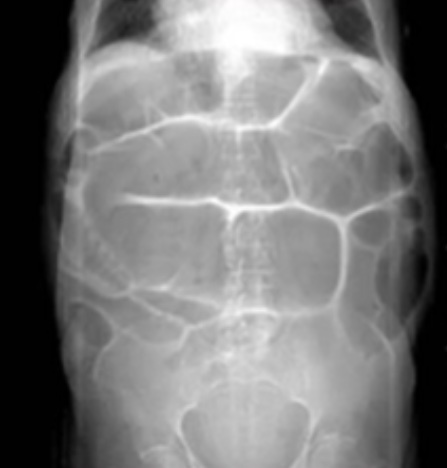

Qual o diagnóstico?

Obstrução intestinal baixa